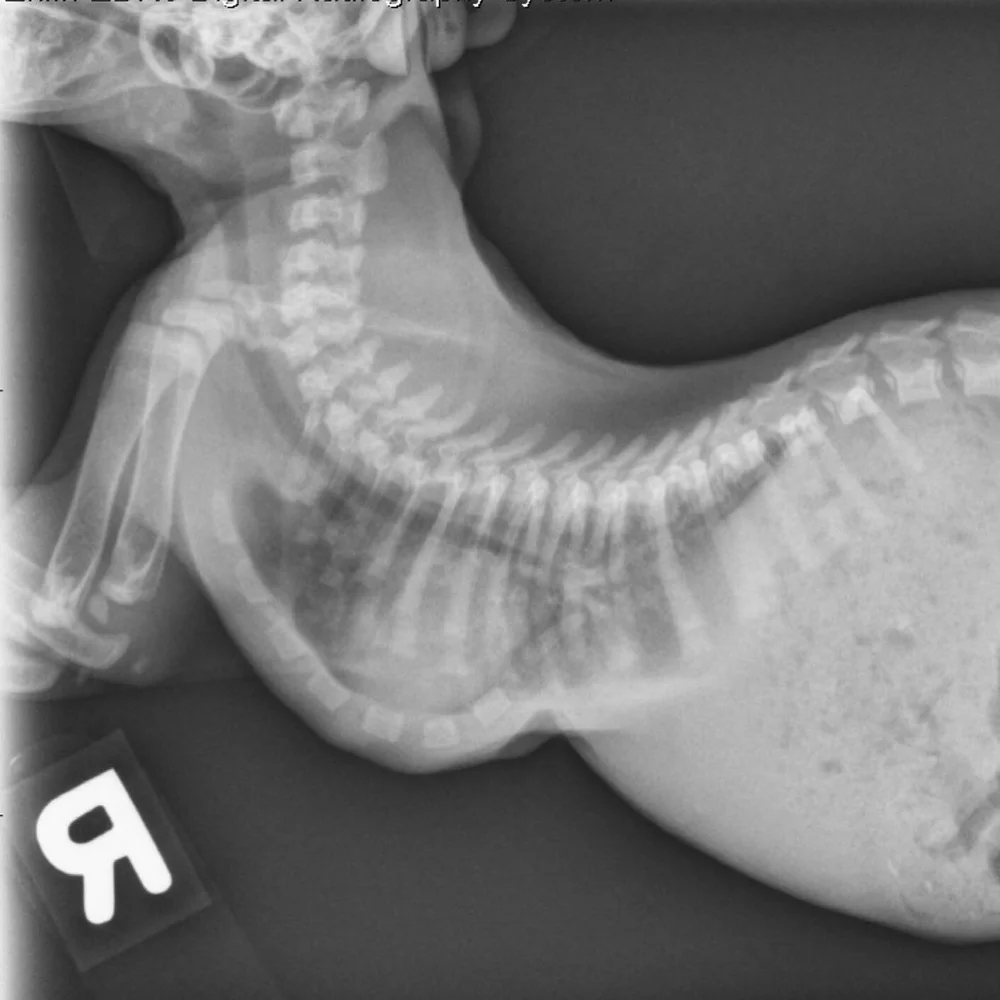

Minimally Invasive Repair Of The Severe Pectus Excavatum In An Infant Sciencedirect

Pectus Excavatum In Puppies And Kittens Mspca Angell

Pectus Excavatum In Kittens Kitten Lady